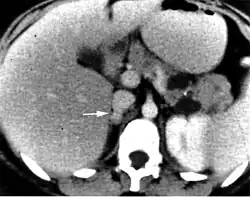

An adrenal incidentaloma is an adrenal tumor found by coincidence without clinical symptoms or suspicion. It is one of the more common unexpected findings revealed by computed tomography (CT), magnetic resonance imaging (MRI), or ultrasonography.[18][19] Adrenal incidentalomas often secrete cortisol and require thorough clinical evaluation.[19][20]

Management of incidentalomas include evaluation by a endocrinologist or endocrine surgeon.[14] Tumors under 3 cm are generally considered benign and are only treated if there are grounds for a diagnosis of Cushing's syndrome or pheochromocytoma. Radiodensity helps with estimating the risk of malignancy in a tumor. A tumor of 10 Hounsfield units or less on an un-enhanced CT is likely a lipid-rich adenoma.[21]

On CT scan, benign adenomas typically are of low radiographic density (due to fat content) and show rapid washout of contrast medium (50% or more of the contrast medium washes out at 10 minutes). If the hormonal evaluation is negative and imaging suggests benign, follow-up should be considered with imaging at 6, 12, and 24 months and repeat hormonal evaluation yearly for 4 years.[22]

Adrenal-dedicated CT and MRI imaging can be performed to distinguish benign adenomas from potentially malignant lesions.[23][24] Online calculators assist radiologists in calculating the washout of contrast in adrenal nodules on CT[25] and chemical shift on MRI.[26]